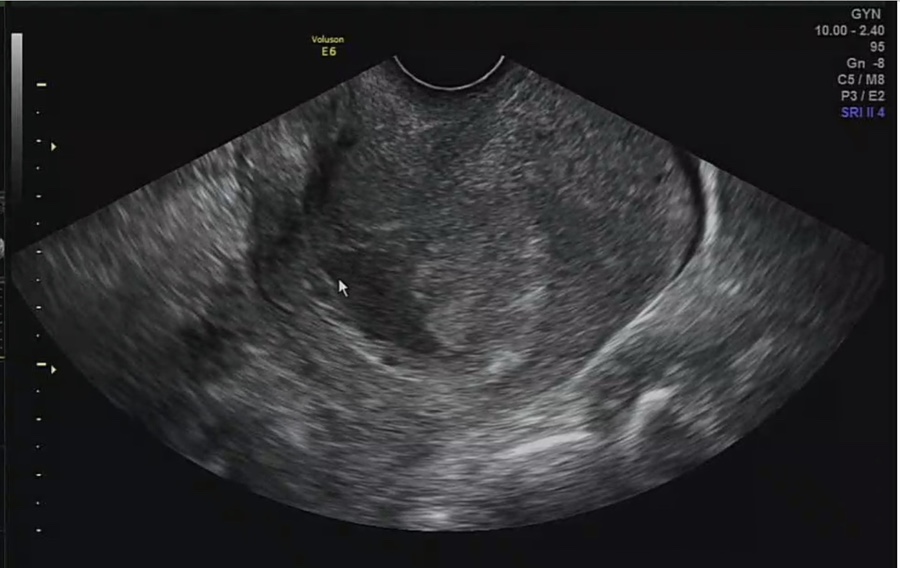

저번 5주4일에 아기집만 보고 노른자, 아기를 못봤다고 하였는데 6주0일에 다른병원에 가서 노른자, 아기(배아)를 보고와서 다 건강하니 2주후 8주에 오라고 하셔서 6주에 산전검사를 하고왔는데

어쨌든내과진료와함께산부인과도진료를받아야된다면서진료를받는김에아기가잘있는지살펴보자고해서보고왔는데,

임신 7주 2일 심장 소리를 듣는다!

일단 저번보다 아기가 많이 컸다고 비춰주셨어요 아기의 크기는 1.1cm, 7주, 1일 정도로 예상 주수에 맞게 커진다고 합니다.